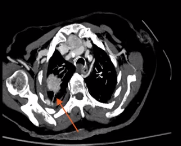

18G 半自动共轴穿刺三次取样后,显示预期的肺泡出血和轻微咳血。4小时后患者出现低容量,立即进行CTA。

| CT扫描并没有看见预期中肋间动脉出血,可见造影剂经针道外溢至游离胸膜腔,形成血胸 | |

由于患者快速恶化,会诊后经血管内栓塞成为选择

肺动脉血管造影显示肺动脉分支持续外渗至胸膜腔。右侧经右股总静脉置换5 Fr C2诊断导管。

然后使用2.4F同轴微导管使用微弹簧栓子栓塞出血血管,用明胶海绵胶浆辅助弹簧栓子栓塞以达到更快的栓塞效果。一周后患者从出血事件康复出院